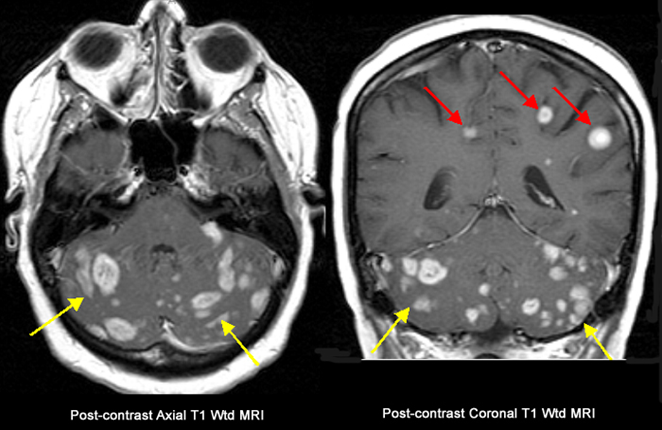

Peak incidence 50-60 years

Neoplasm occupies both hemispheres through the corpus callosum

Irregular ring enhancing

Average 1 year survival

GBM

astrocytoma who grade 4

ring enhancing T1

crosses corpus callosum

necrosis in the middle

(This pattern could be GBM, abccess with correct picture of infection ,or primary CNS lymphoma, but most likely GBM)

Butterfly lesion

astrocytoma grade 4